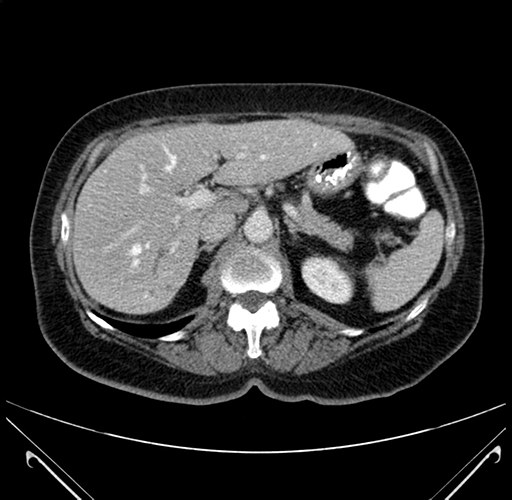

Coronal Venous